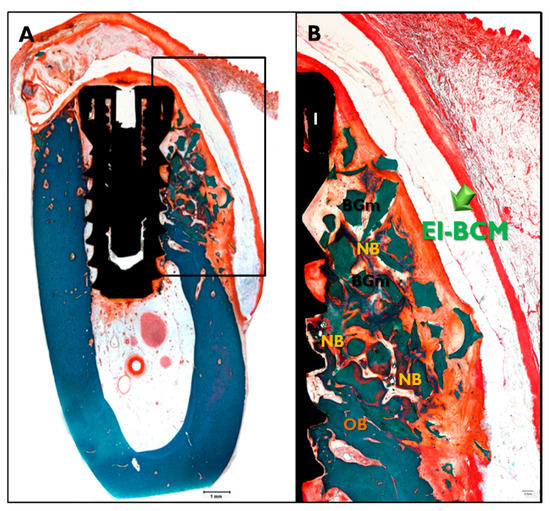

In the CM transplanted animals (Figure 8), a new bone formation was observed and fibrous connective tissues and graft materials were also observed in buccal peri-implant dehiscence defect areas. In some specimens, small amounts of membranes were observed. In the EI-BCM and CM transplanted animals (Figure 9), new bone, fibrous connective tissue, and graft materials were observed in the peri-implant dehiscence defect area. The EI-BC membranes remained at eight weeks in a similar pattern to the CM group, but expansion of the membrane was observed in some specimens.

Figure 9.

Histological sections specimen in EI-BCM transplanted animal. NB, new bone; BGm, bone graft material; OB, old bone; I, implant (Goldner Trichrome stained; original magnifications: 12.5× (A); and 40× (B)).